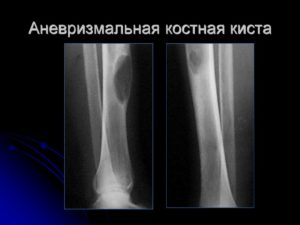

- Аневризмальную, которая возникает почаще у девченок, она заполнена кровью.

Таковая киста возникает пореже, чем солитарная, возникает в большей степени у девченок от 10 до 16 лет, поражает традиционно тазовые кости и позвоночник.

Так же как и солитарная киста, аневризмальная равномерно теряет питание и миниатюризируется в размере, остается остаточная полость или участок патологического разрастания костной ткани.